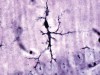

Examining human brain tissue was once the only way to make a firm Alzheimer’s diagnosis.Credit: Westend61/ Getty Images